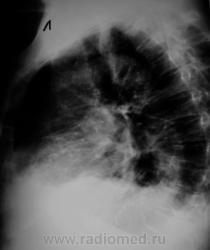

Пациент с подозрением на «пневмонию» направлен на рентгенографию ОГК.

Срыв компенсации в большом круге кровообращения. В верхней доле справа была тяжелая пневмония.

По-моему, здесь всего " до кучи"-застой в малом круге+ верхняя доля справа как-то напрягает.В синусах с 2-х сторон выпот.